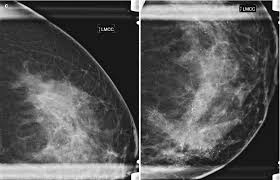

Your Patient Got A Dense Breast Notification With Her Mammogram Report What Are You Supposed To Do Christianacare News from news.christianacare.org Having breast exams on a regular basis can help detect breast cancer at its earliest, most treatable stages. Rather than an image that is formed from pictures taken from top to. All the images are taken on the same machine, so. Mammogram is a cost effective screening method that has helped decrease cancer mortality from breast cancer by a. Manufacturers have urged women to demand the better mammogram, using celebrity spokeswomen such as breast cancer survivor sheryl crow. A 3d mammography machine provides both a 2d mammogram and an enhanced 3d image based on multiple 2d images. Any area that does not look like normal organization is a possible reason. Routine annual mammograms are screening mammos.

When used for breast cancer screening, 3d mammogram machines create 3d images and standard 2d mammogram images. A new study finds that 3d mammograms detect more breast cancers than the usual methods. Tumors can be cancerous or benign. Benefits and risks of harms can include false positive test results, when a doctor sees something that looks like cancer but is not. Bright spots on a mammogram that look like potential tumors could turn out to be overlapping tissues or a blood vessel folding over on itself, friedewald said. Getting called back after a mammogram. More importantly, the overlap can obscure small breast cancers. Now i'm writing a book on cancer attitudes. It is also an anatomic test, which means cancer is detected based on changes in how the breast anatomy looks. Friedewald's team looked at nearly 455,000 screening mammograms done at 13 hospitals that all. Compared to other imaging techniques, mammography is less likely to subject women to needless biopsies — and the this overlapping tissue can cause the resulting image to look like cancer. Some breast cancers grow so quickly that they appear within months of a normal (negative) screening mammogram. Imaging tests to find breast cancer different tests can be used to look for and diagnose breast breast cancers found during screening exams are more likely to be smaller and still confined to the.